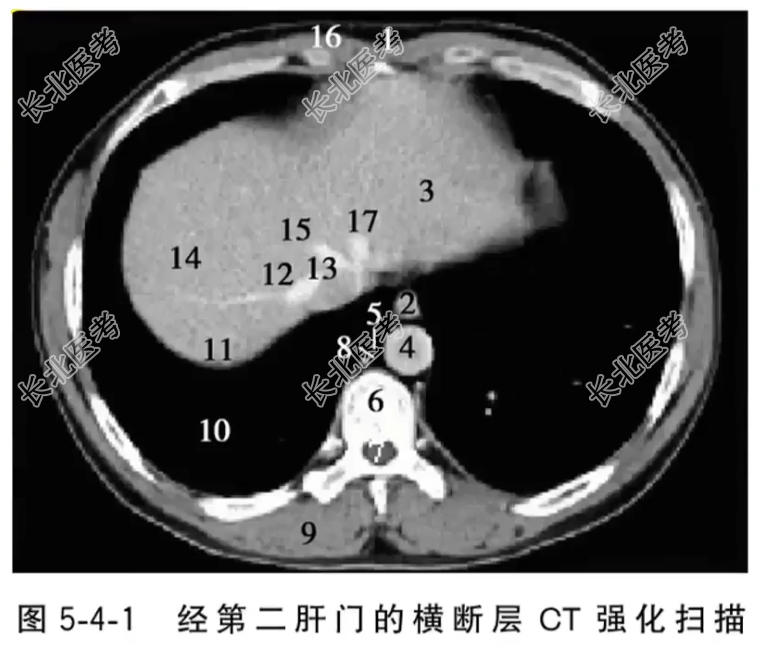

- 单项选择题经第二肝门的横断层CT强化扫描图像中,标记为13的结构是

A、食管

B、胸主动脉

C、下腔静脉

D、肝右静脉

E、肝左静脉